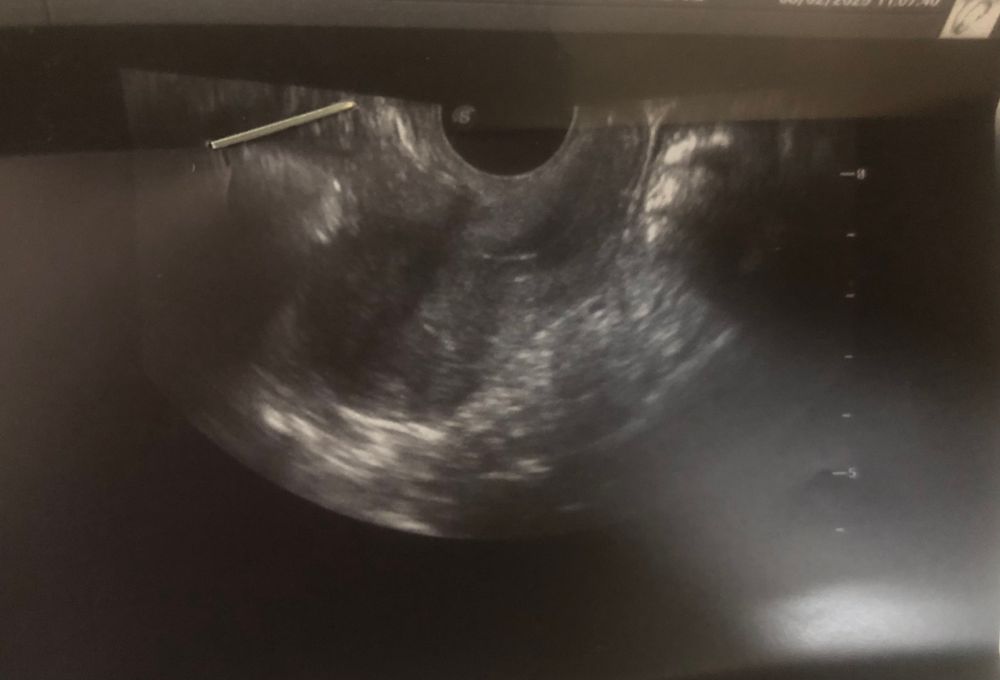

Левый яичник прижат к матке, у кого была такая ситуация? Возможна ли беременность 🥹

Здравствуйте, у меня такая проблема, что яичник прижат к матке, обе трубы проходимы, проверяла на ГСГ, месячные регулярные, 30-35дней.

Кто был в такой ситуации? Что вы сделали? Возможна ли беременность?🥹